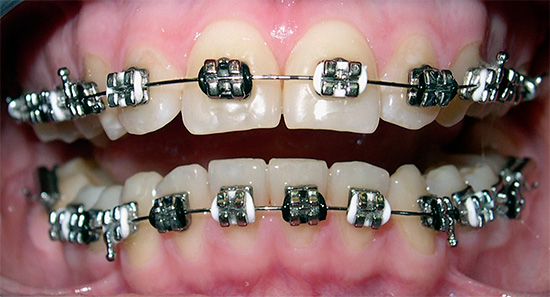

L'uso del sistema a staffa nel trattamento della malocclusione è il metodo di scelta (anche in età adulta). Che cos'è un sistema di staffe? In termini semplici, le parentesi graffe sono dispositivi fissi fissati ai denti, con blocchi, in cui è incorporato un programma speciale per lo spostamento dei denti. Il movimento viene eseguito a causa dell'arco, che è fissato in questi blocchi, l'arco si muove e raggiunge la forma ideale dell'arco dentale.

- parentesi graffe, ovvero, l'arco è legato alla staffa mediante speciali legature in metallo o gomma. Le legature forniscono una rigida adesione dell'arco alla staffa e limitano lo scorrimento lungo l'arco dentale. Lo svantaggio di questa attrezzatura è la necessità di frequenti visite dal medico una volta al mese (e alcuni medici prescrivono i pazienti ogni due settimane). Le visite sono necessarie per sostituire le legature, poiché tendono a indebolirsi.

- I più semplici e evidenti sono le parentesi graffe metalliche. Il loro vantaggio è che sono molto resistenti. Se la staffa si stacca, può essere incollata di nuovo. La pratica dimostra che le parentesi graffe metalliche garantiscono una riduzione dei tempi di trattamento per un morso anomalo.